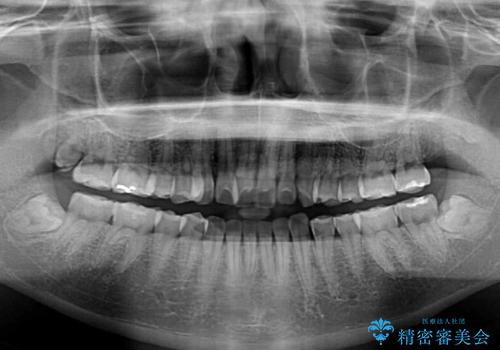

- 前歯のデコボコと、上下前歯が接触せずに前に飛び出していることを気にして来院された患者様です。

舌の突出癖が強く、それが原因で上顎歯列全体が前方に突出し、上下前歯が接触できない状態となっていました。

補助装置を用いて上顎臼歯を後方移動させ、歯列を整えながら前歯部の接触を図ることとしました。